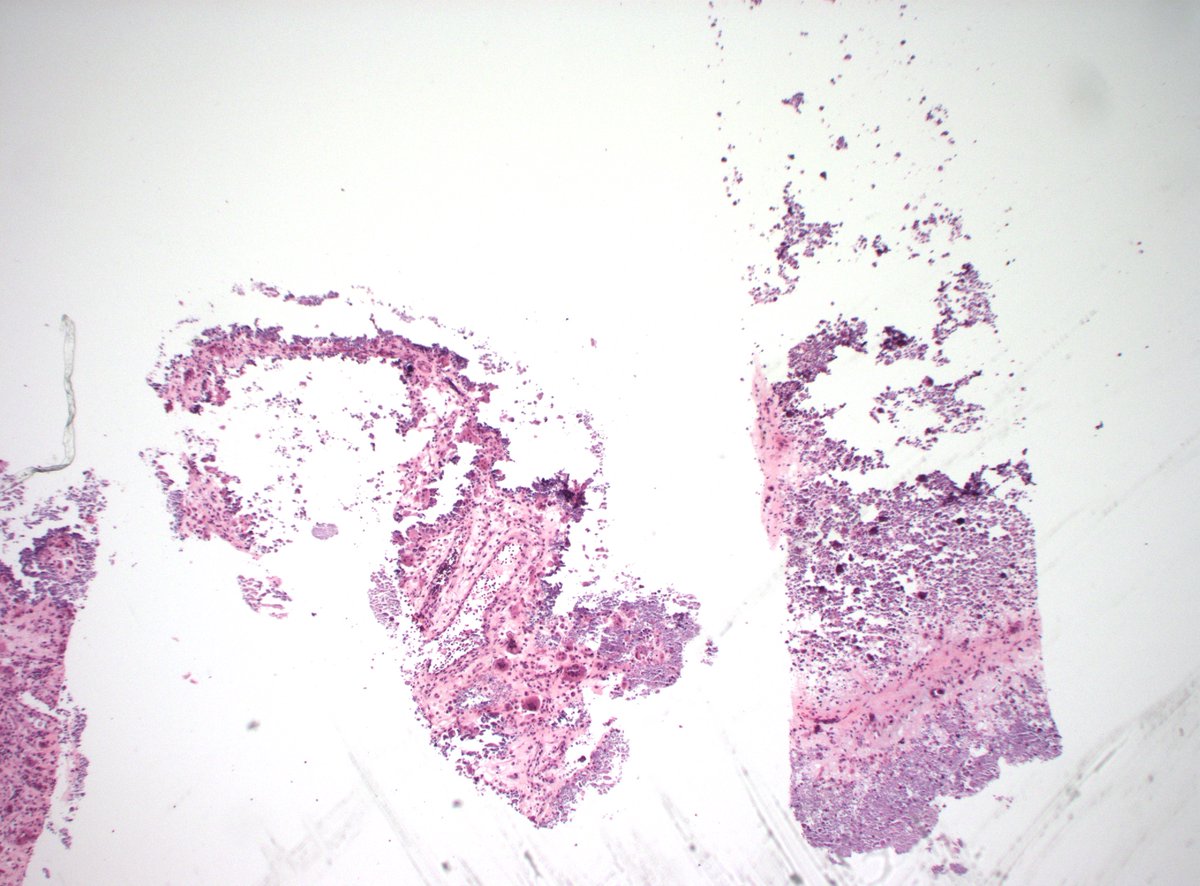

For all the pain & agony that endometriosis causes, WHY are peritoneal biopsies almost always crap? Is this just in the places I've worked?

Look at this cauterized piece of junk. Leveled through & still no evidence of endometriosis.

#gynpath #obgyn #pathtwitter #medtwitter